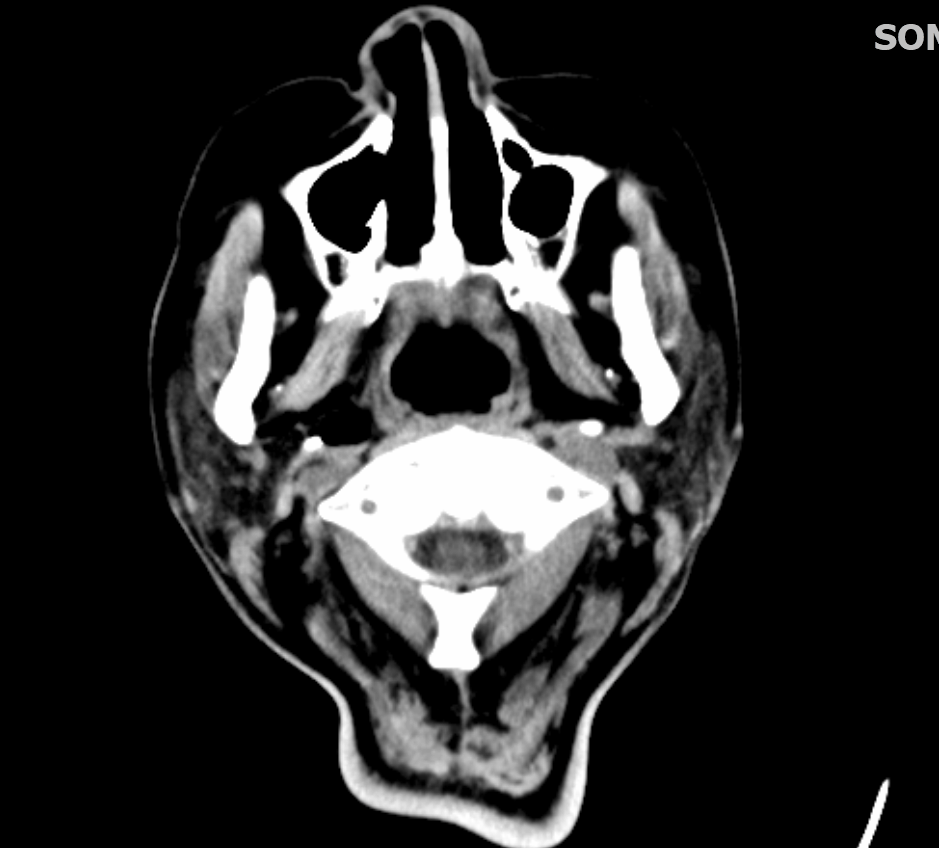

病患因為有明顯外傷且意識不清,後續做了Brain CT and Whole body CT。

Brain CT顯示有左側的SDH與雙側Tentorium SDH

Whole body CT看到肋骨骨折、鎖骨骨折,肩胛骨骨折